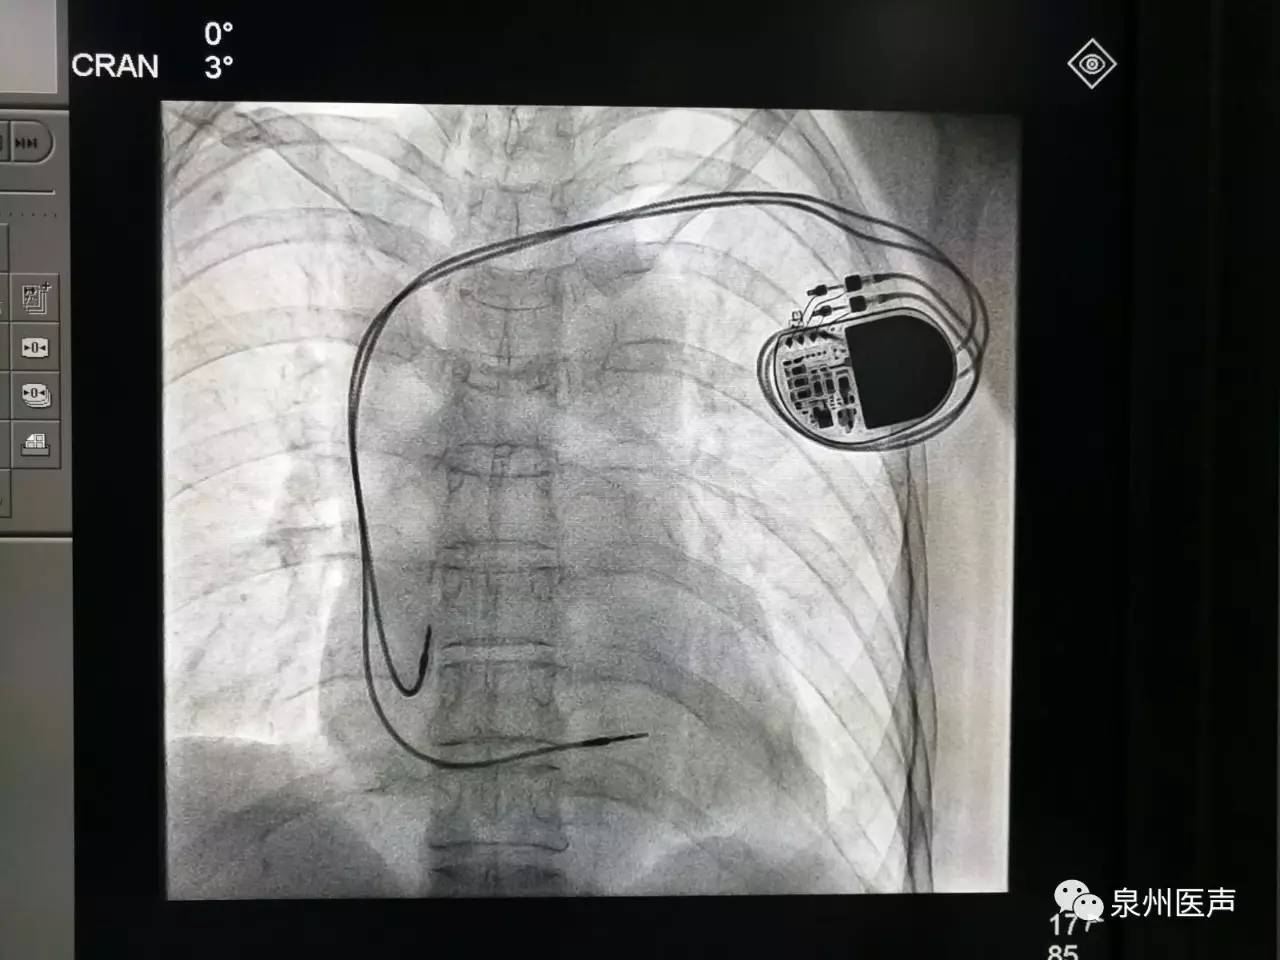

心臟起搏器的日常護理

心臟起搏器出院的宣教,是心內(nèi)科醫(yī)護人員不容忽視的一項工作